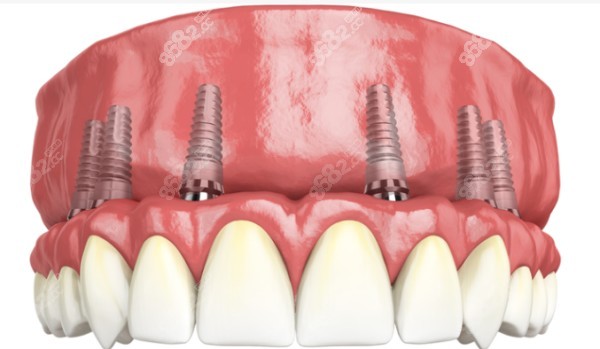

衡阳即刻负重半口种植牙价格:5-10万元左右

即刻负重技术是现在比较常用的种植牙技术,因为不用漫长的等待期~86/82,可以实现当天种牙,当天吃东西的愿望,因此还是蛮受欢迎的<cc。